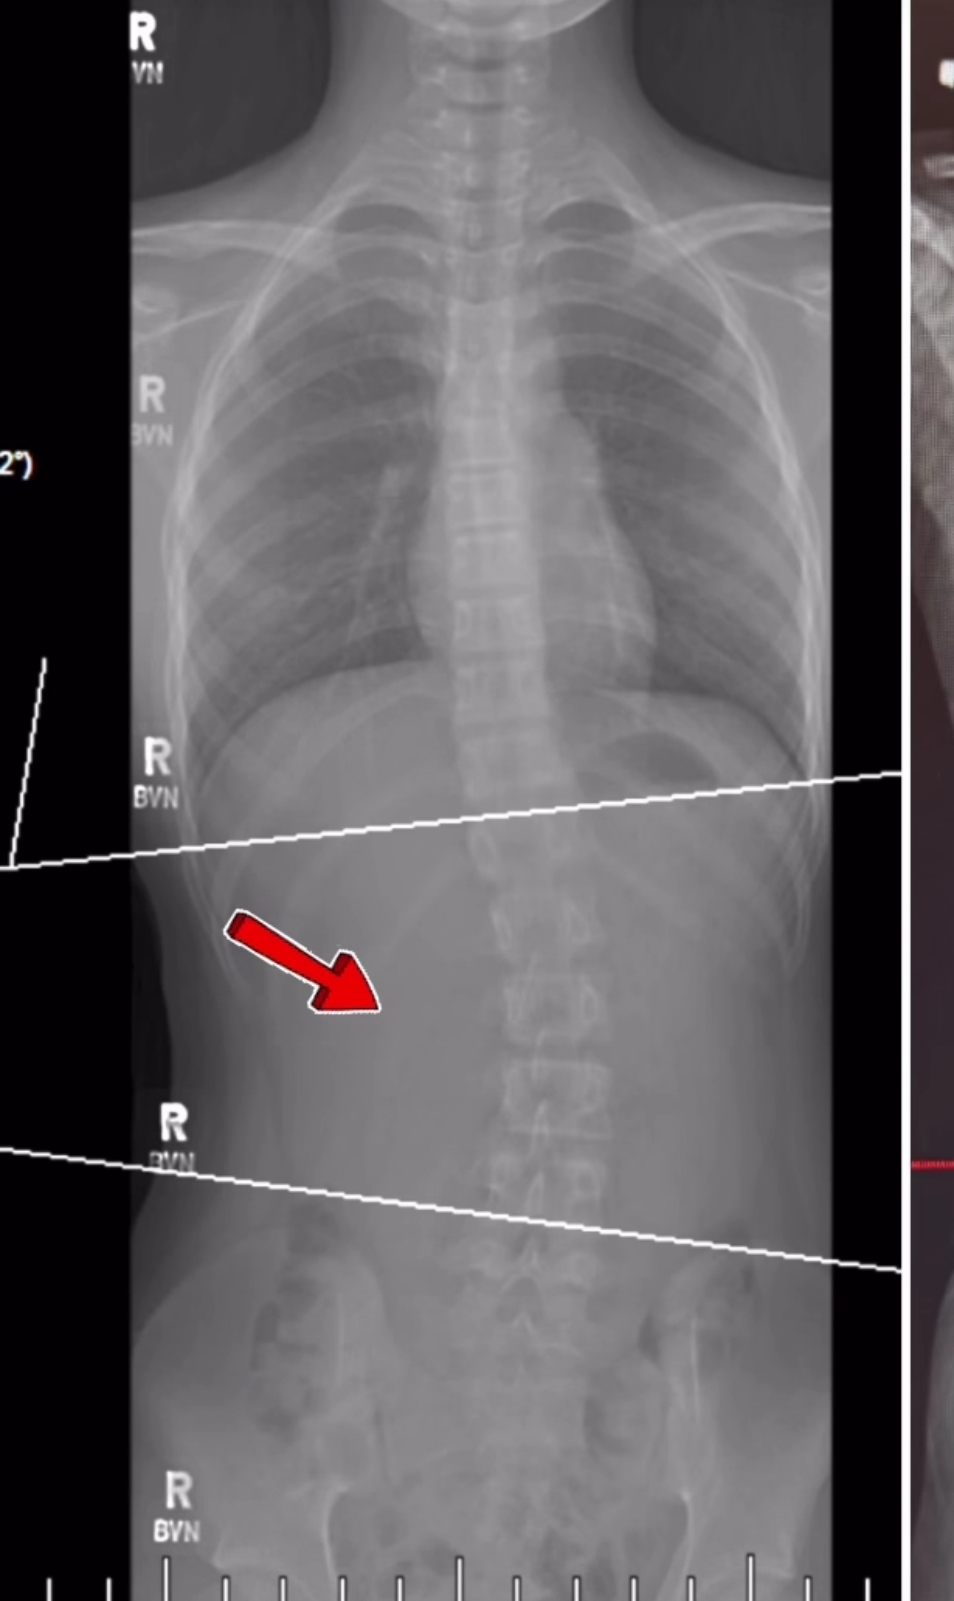

이 엑스레이 사진을 보고 이렇게 말합니다.

척추가 휘었네

결과적으로 척추가 휘었어요

근육이 한쪽이 짧은 겁니다. 근육이 굳어서 짧아진 겁니다.

근육을 풀어주어 자세를 유지하도록 하면 됩니다